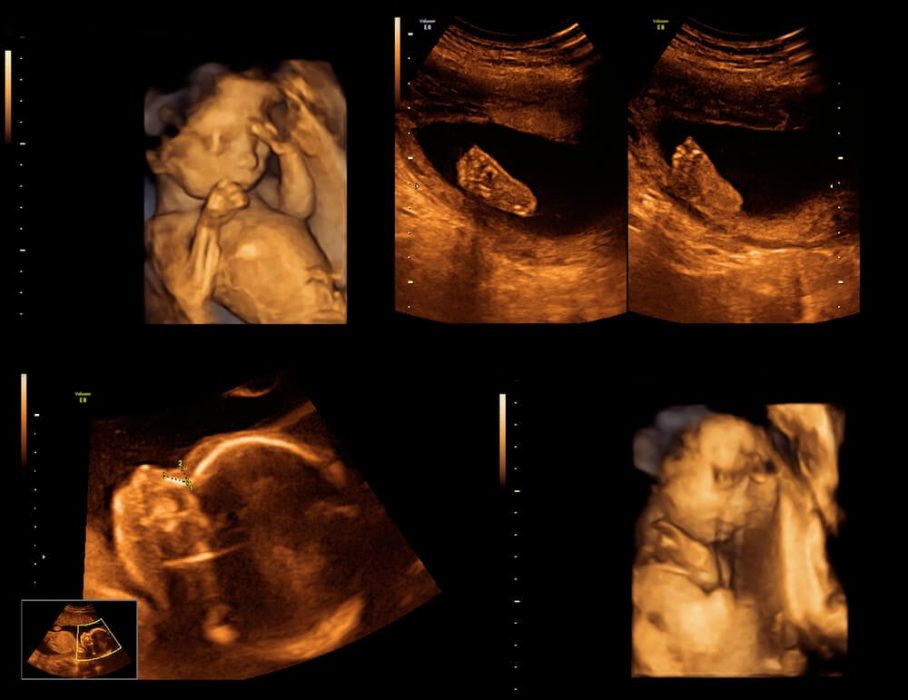

Üç-dört boyutlu ultrasonografi

Genellikle fetusun yüzünün ve diğer organlarının renklendirilmiş şekilde görüntülenmesini sağlayan, renkli fotoğrafa benzeyen, bilimsel kullanıma yaygın olarak geçmemiş, biraz da estetik ve ticari amaçla kullanılan yöntemdir. Gereksiz yere birden fazla yapılmasının yararı veya zararı henüz bilinmemektedir.